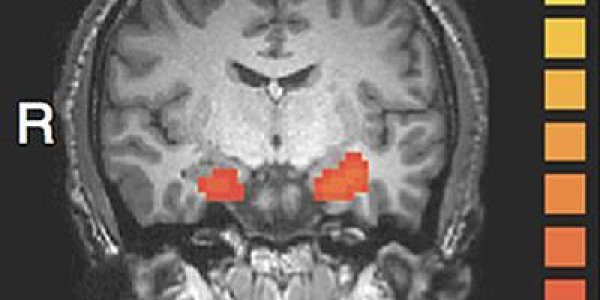

Anxiety Linked To Seizures Mistaken For Epilepsy

New research has revealed psychogenic seizures which could be mistaken for epilepsy are linked to feelings of anxiety. The team of researchers devised a set of tests to determine whether there was a…